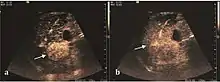

These lesions have various patterns (hypo or hyperechoic) with at least 1 cm diameter. They are hepatocytes with dysplastic changes, but without clear histological criteria for malignancy. They are divided into low-grade dysplastic nodules, where cellular atypia are mild and high-grade dysplastic nodules with moderate or severe cellular atypia, but without any established signs of malignancy. Occasionally, well-differentiated HCC foci can be identified in high-grade dysplastic nodules (appearance called "nodule in nodule") . Most authors accept the carcinogenesis process as a progressive transformation of DN from low-grade to high-grade and into HCC. The nodule's vasculature changes progressively, correlated with the degree of malignancy, and it is characterized by decrease until absence of portal venous input and by increase of arterial intratumoral input. Neoformation vessels occur with increasing degree of dysplasia. Arterial neovascularization is enhanced in a chaotic and explosive way, while normal, arterial and portal vasculature continues to decline. High-grade dysplastic nodules are hypovascularized both arterial and portal phases, while early HCC nodules may have similar arterial pattern with the surrounding parenchyma or exacerbated, and portal hypovascularization. In moderate or poorly differentiated HCC (classic HCC) tumor nutrition is performed only by neoformation vessels (abundant), the normal arterial and portal vasculature completely disappearing. This behavior of intratumoral vascularization is typical for HCC and is the key to imaging diagnosis.

B-mode ultrasonography is unable to distinguish between regenerative nodules and borderline lesions such as dysplastic nodules and even early HCC. Doppler examination also has a low sensitivity in differentiating dysplastic nodules from early HCC. Doppler signal may be absent in both regenerative and dysplastic nodules. Some authors indicate the presence of venous type Doppler flow which reflects the portal venous nutrition of the nodule as a characteristic feature of dysplastic nodules and early HCC (Minami & Kudo, 2010). Other authors noticed the presence of an arterial flow with small frequency variations and a normal resistivity index. On CEUS examination both RN and DN may have quite a variable enhancement pattern. Generally, both nodules enhances identically with the surrounding liver parenchyma after UCAs injection. Dysplastic nodules are hypovascular in the arterial phase. In case of highgrade dysplastic nodule sometimes a hypervascularization can be detected, but without associating "wash out" during portal and late CEUS phases. In these cases, biopsy may clarify the diagnosis.

The suggestive appearance of early HCC on 2D ultrasound examination is that of hypoechoic nodule, with distinct pattern, developed on cirrhotic liver. Hypoechoic appearance is characteristic of moderate/poorly differentiated HCC, with low or absent fatty changes. Rarely, HCC may appear isoechoic, consist of a tumor type with a higher degree of differentiation and therefore with slower development. Another common aspect is "bright loop" or "nodule-in-nodule" appearance, hypoechoic nodules in a hyperechoic tumor.

On CEUS examination, early HCC has an iso- or hypervascular appearance during the arterial phase followed by wash out during portal venous and late phase. There are studies showing that the wash out process is directly correlated with the size and features of neoplastic circulatory bed. Thus, highly differentiated HCC illustrates the phenomenon of late or even very late "wash out" while poorly differentiated HCC has an accelerated wash out at the end of arterial phase. It is therefore mandatory to analyze all these three phases of CEUS examination for a proper characterization of liver nodules. Tumor wash out at the end of the arterial phase allows the HCC diagnosis with a predictability of 89.5%. Some authors consider that early pronounced contrast enhancement of a nodule within 1–2 cm developed on a cirrhotic liver is sufficient for HCC diagnosis. These results prove that for a correct characterization of the lesions it is necessary to extend the examination time to 5 minutes or even longer.